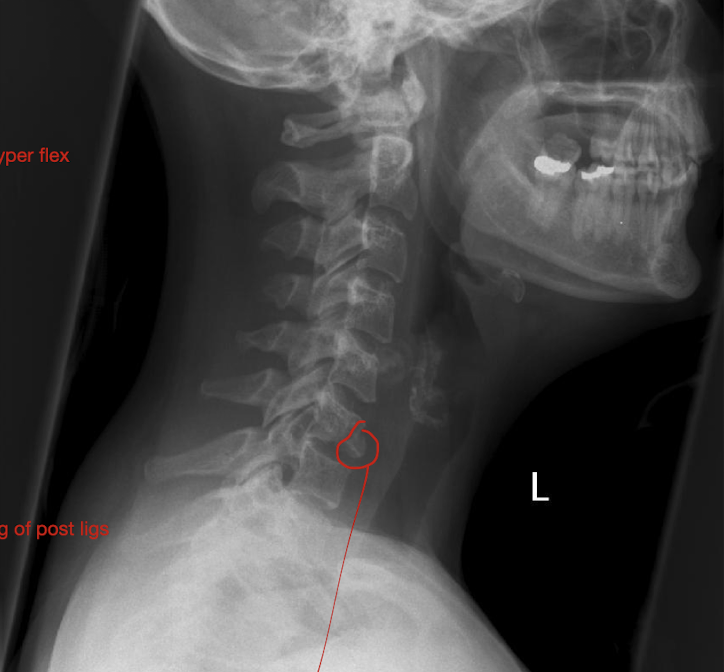

Fracture of C3-C7: Tear Drop Fx

What is this fx known as?

How does it occur?

2

Known as:

Most severe of the Lower C/S Fx (Hyper Flexion)

How:

Separation of a piece of bone from the Anterioinferior border of the vertebral border

Hyperflexion or Hyperextension

Fracture of C3-C7: Tear Drop Fx

How much force causes pieces to rupture off and tearing of post ligs.

Stable or Unstable Injury

Large Force

Unstabble